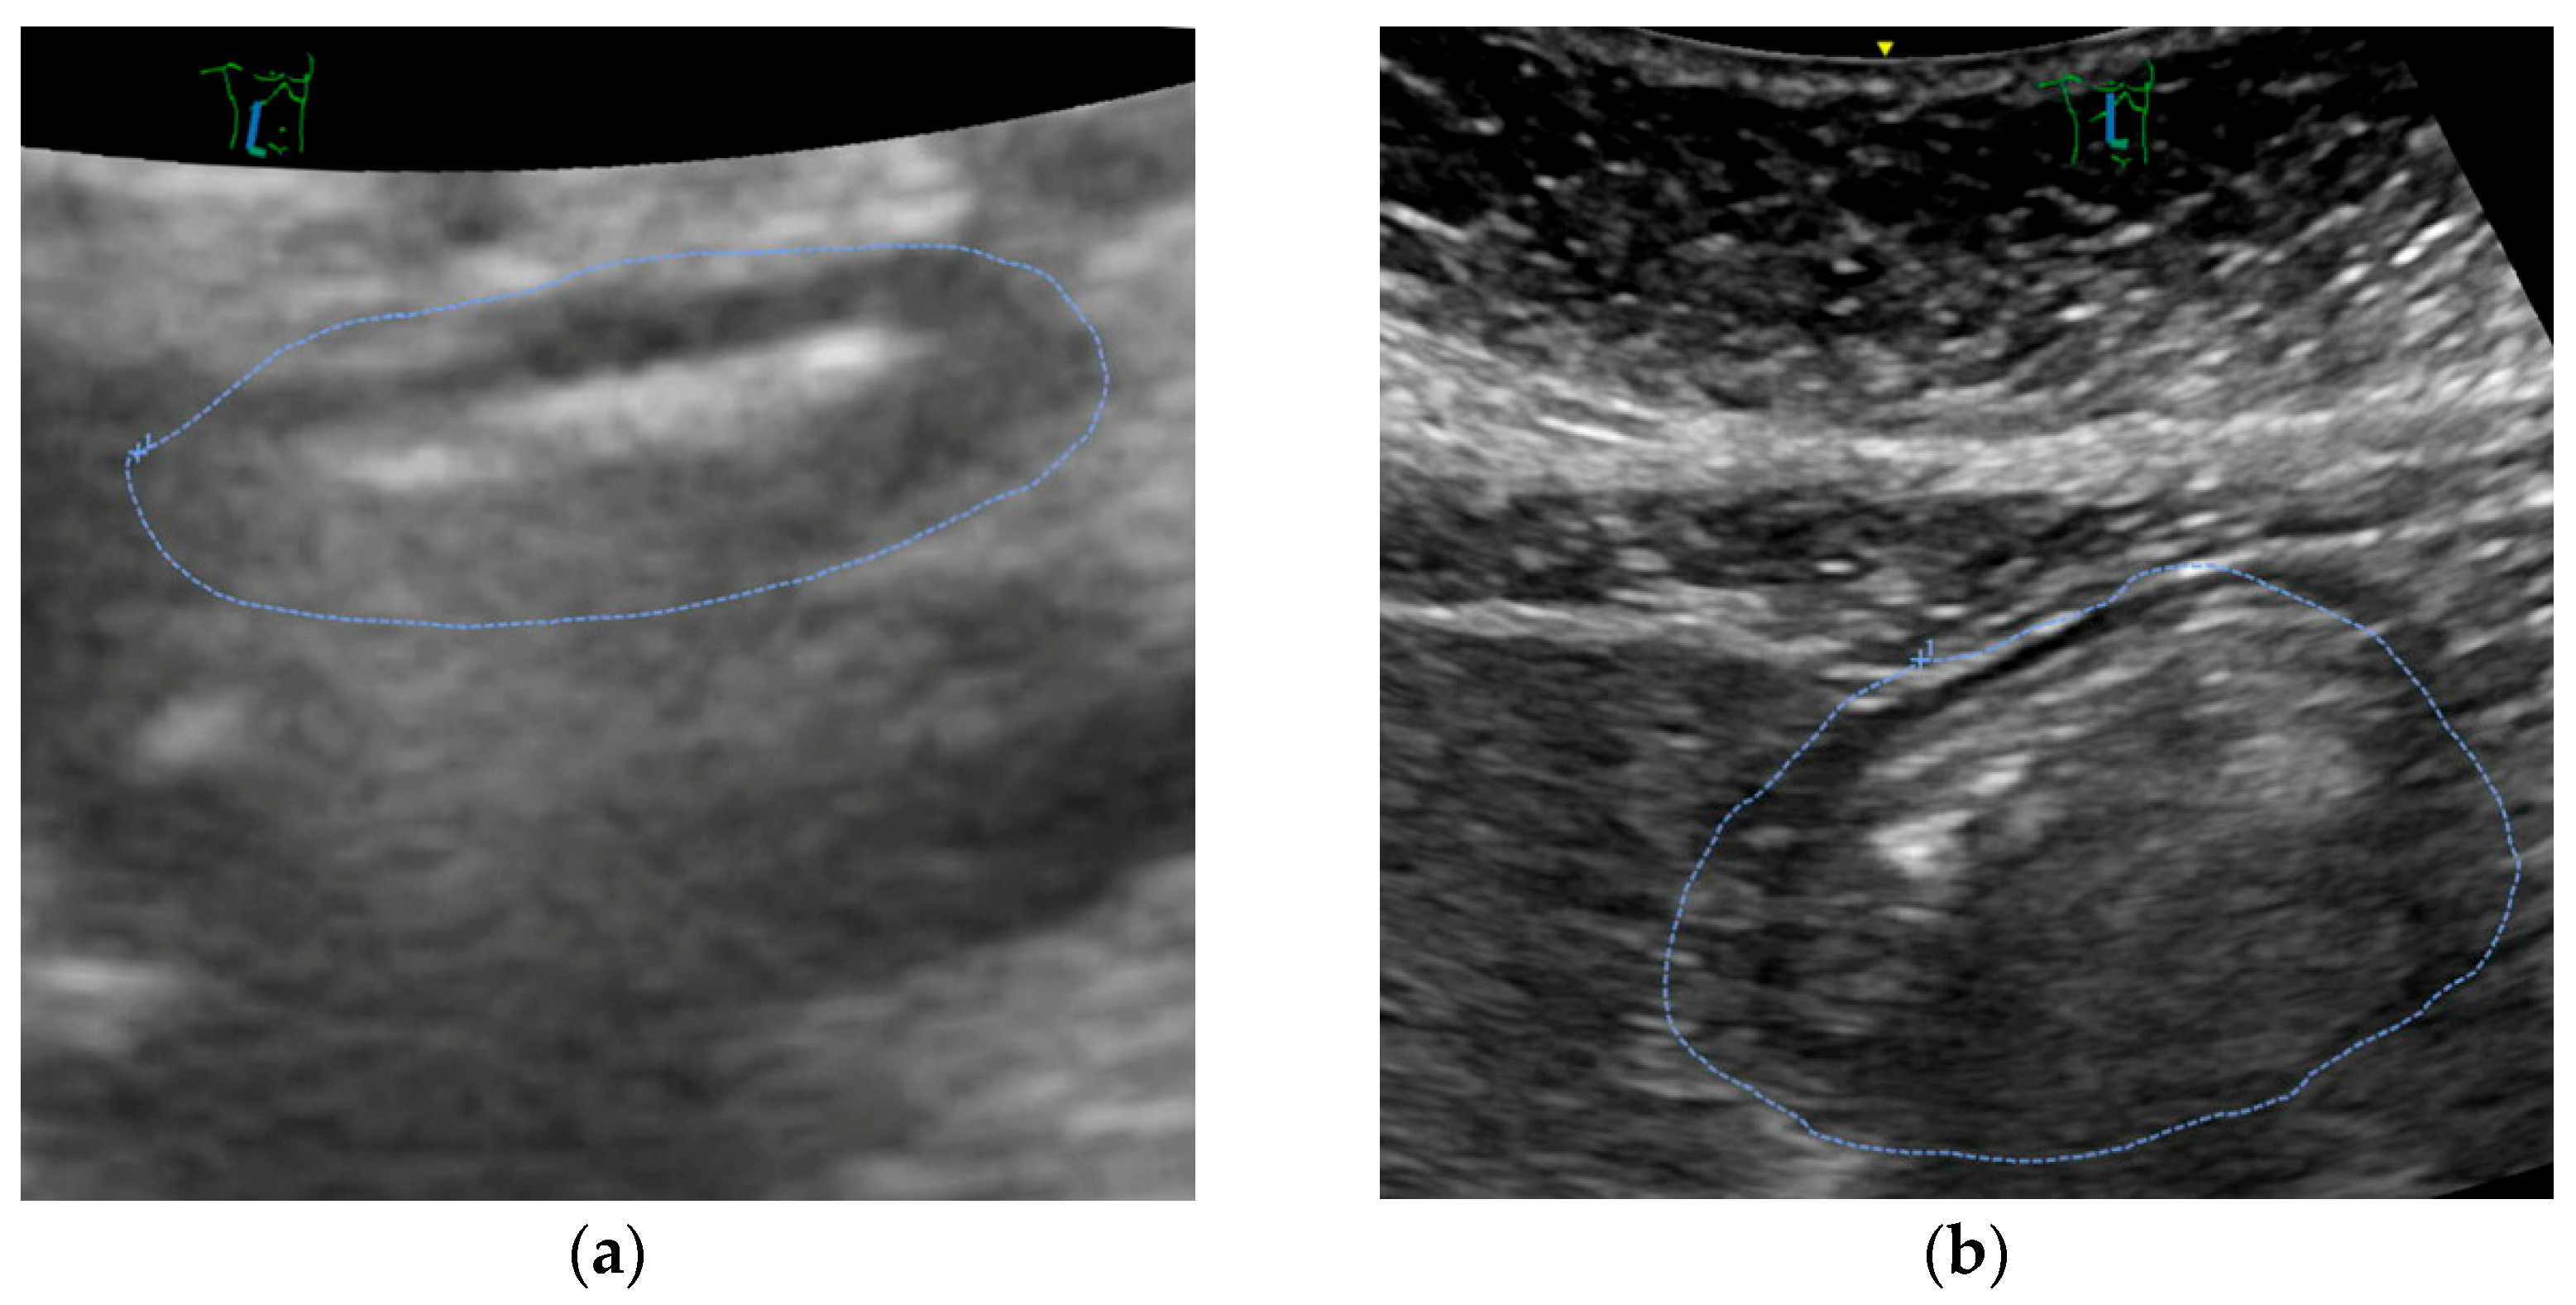

Figure 2 shows the antral cross-sectional area of patients before and after the implementation of the liberal fluid fasting concept and reveals only a slight increase in gastric content.

Mostly, ultrasound revealed an empty stomach (Figure 3a). In some patients, we found proof that tablets were taken in the morning or immediately before the call for theatre. Only in a small number of patients, remnants of clear liquids were documented (see Figure 3b). No solids were encountered.

Figure 3. Screenshot of a representative gastric ultrasound exam performed in a patient (a) with an empty stomach (CSA 2.98 cm−2 corresponding to a calculated gastral volume of 70.5 mL) and (b) with a full stomach (CSA 12.0 cm2, 202 mL). Both patients had no liquids for more than two hours before the exam.